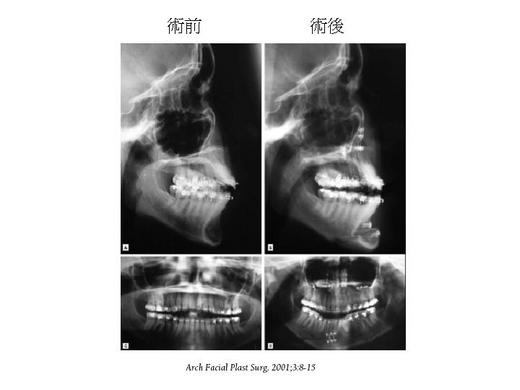

The chin, one of the most obvious facial structures, plays an important role in the perception of the face. Horizontal sliding Osteotomy of the mandibular symphysis with advancement of the mobilized segment is the technique of choice for correction of the anterior posterior deficiency. Sliding genioplasty can be an adjunctive procedure to rhinoplasty if the patient has a weak chin and wants a more harmonic face features.

On the contrast, sliding genioplasty can decrease the projection of chin if the patient has a strong chin (macrogenia).